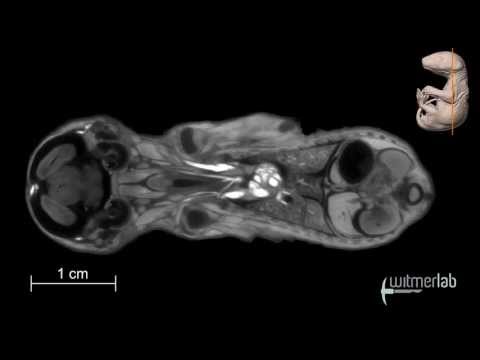

Visible Interactive Opossum - transverse slice movie of a µCT-scanned opossum joey

Virginia opossum : 北オポッサム Autopsy imaging